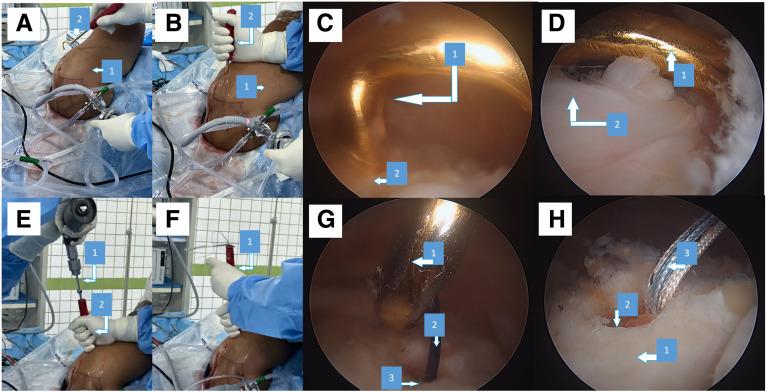

Performed and taught multiple surgeries including Stryker Reverse Replacement , Ax Cuff repair , Ax AC joint excision , Trapeziumectomy FCR suspensionplasty

Had number of discussions on Reverse shoulder replacements , Just Unic , Transosseus cuff repairs and more